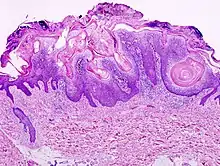

Visual diagnosis is made by the "stuck on" appearance, horny pearls or cysts embedded in the structure. Darkly pigmented lesions can be challenging to distinguish from nodular melanomas.[8] Furthermore, thin seborrheic keratoses on facial skin can be very difficult to differentiate from lentigo maligna even with dermatoscopy. Clinically, epidermal nevi are similar to seborrheic keratoses in appearance. Epidermal nevi are usually present at or near birth. Condylomas and warts can clinically resemble seborrheic keratoses, and dermatoscopy can be helpful to differentiate them. On the penis and genital skin, condylomas and seborrheic keratoses can be difficult to differentiate, even on biopsy.

A study examining over 4,000 biopsied skin lesions identified clinically as seborrheic keratoses showed 3.1% were malignancies. Two-thirds of those were squamous cell carcinoma.[9] To date, the gold standard in the diagnosis of seborrheic keratosis is represented by the histolopathologic analysis of a skin biopsy.[10]